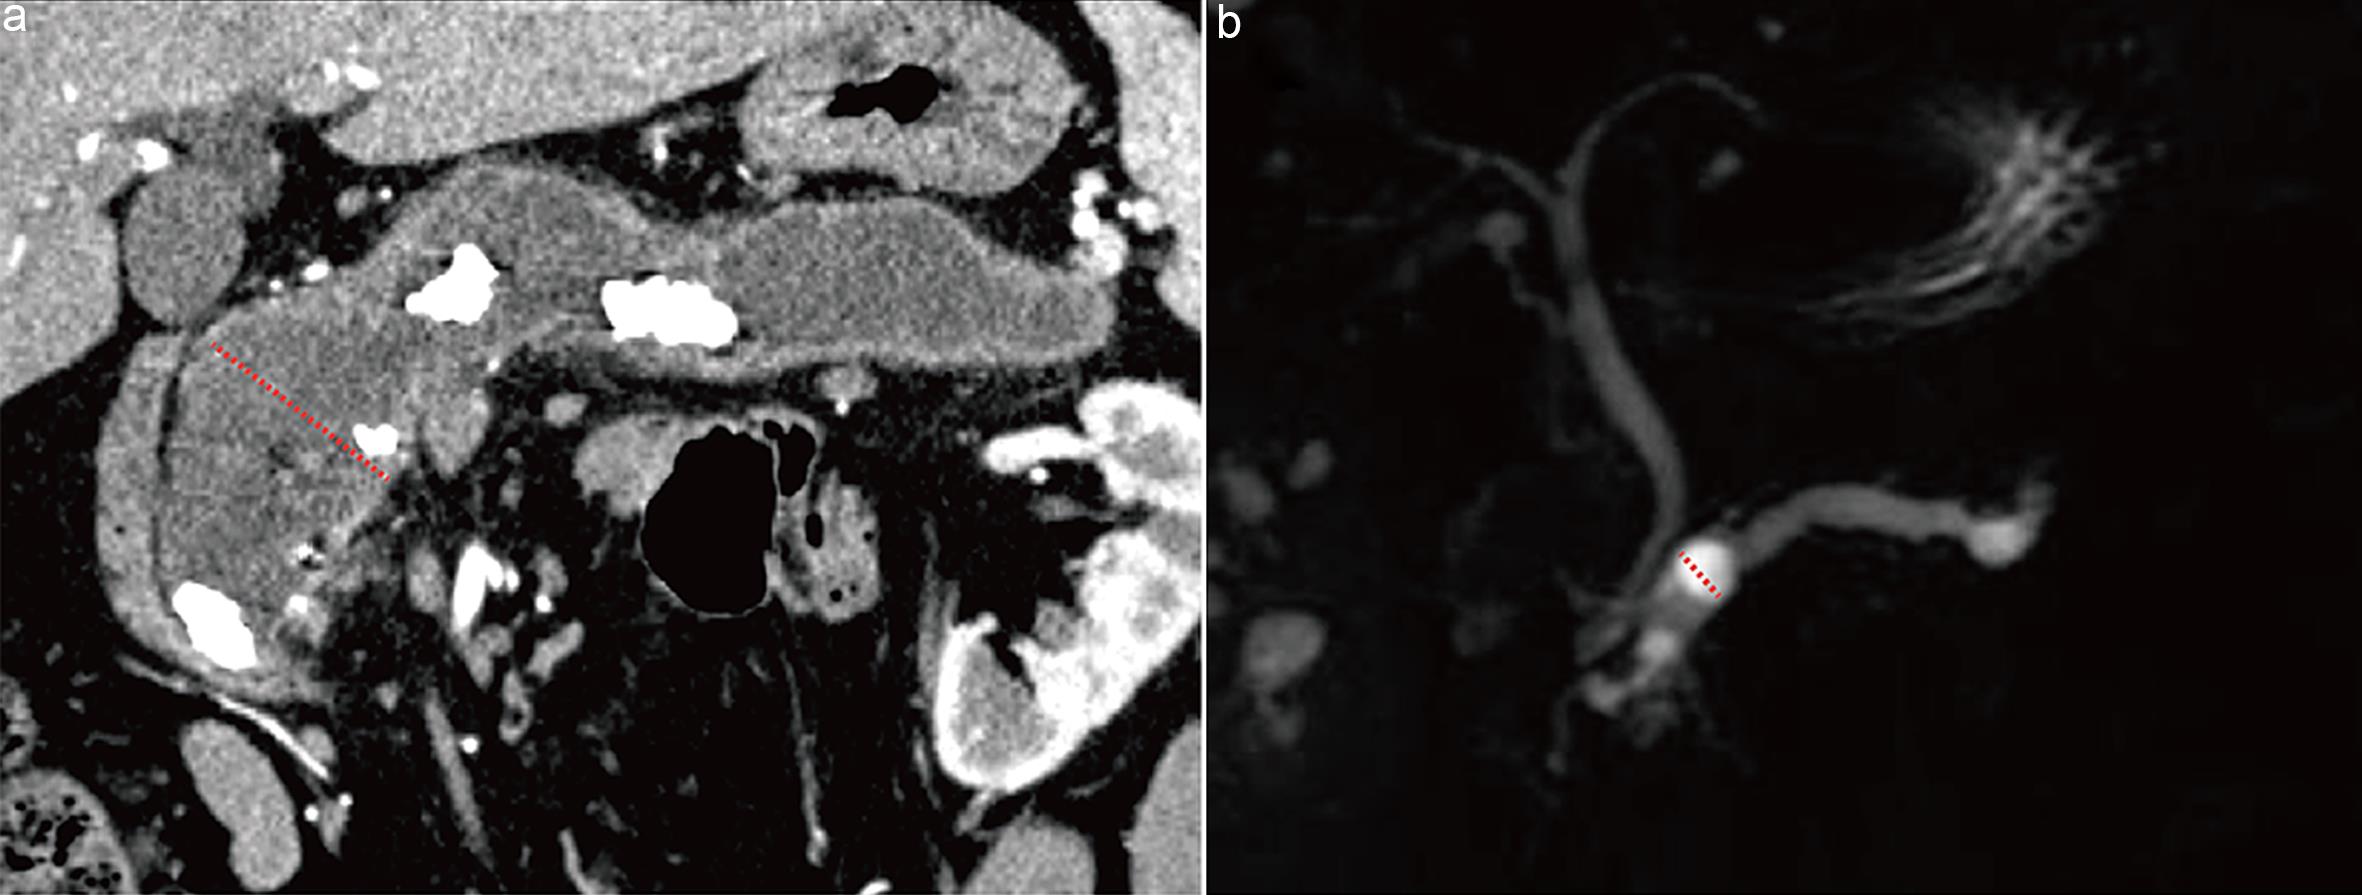

Wall nodules are defined as papillary projections ≥3 mm on the main pancreatic duct wall or cyst wall, associated with malignant tumors (carcinoma in situ or invasive carcinoma).24 For enhancing mural nodules, the pancreatic parenchymal phase of contrast-enhanced imaging provides optimal contrast between normal pancreatic parenchyma and cyst fluid, allowing clear visualization of the cyst wall structure (Fig. 3a). Non-enhancing mural nodules are difficult to visualize on post-contrast images but appear as filling defects on T2WI, where the high signal intensity of cyst fluid provides optimal contrast to delineate the nodule boundaries (Fig. 3b).17

Measurement of mural nodules.

Fig. 3  Measurement of mural nodules.

(a) Axial contrast-enhanced computed tomography (CT) image obtained during the pancreatic parenchymal phase shows an enhancing mural nodule within the main pancreatic duct in mixed-type intraductal papillary mucinous neoplasm (arrow). (b) Axial T2-weighted magnetic resonance image shows a mural nodule within the cystic lesion in a mucinous cystic neoplasm in the pancreatic tail (arrow).

Currently, there is no definitive evidence indicating whether measurement on enhanced images or T2WI is more accurate. In cases of multiple mural nodules, the largest nodule size should be measured. It is important to differentiate mural nodules from mucin balls, which are more common and lack vascular components; mucin balls do not enhance post-contrast and require assessment across multiple sequences to confirm the diagnosis. Fujita et al.25 found that contrast-EUS is superior to CT and MRI in differentiating mucin balls from mural nodules, with detection rates of 100%, 85.7%, and 71.4%, respectively.